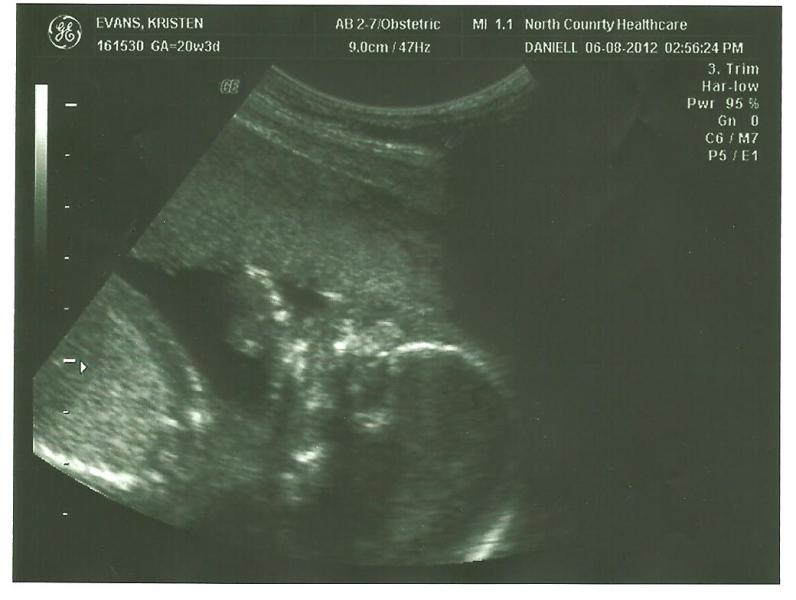

Then on Friday we went to North Country and got right in. The ultrasound technician said that I and our little one were the perfect candidates for an ultrasound and everything was easy to see and read! The spine looked perfect, the heart was working great, and so were the kidneys and the bladder. Everything that was checked looked good! We are so thankful for that! Here are the 5 pictures! :)

This next one is supposedly how they knew it was a girl and not a boy! I really have know clue how they know and would never be able to figure it out on my own! The little white arrows are pointing to the female reproductive organs and the lack of a male reproductive organ :)